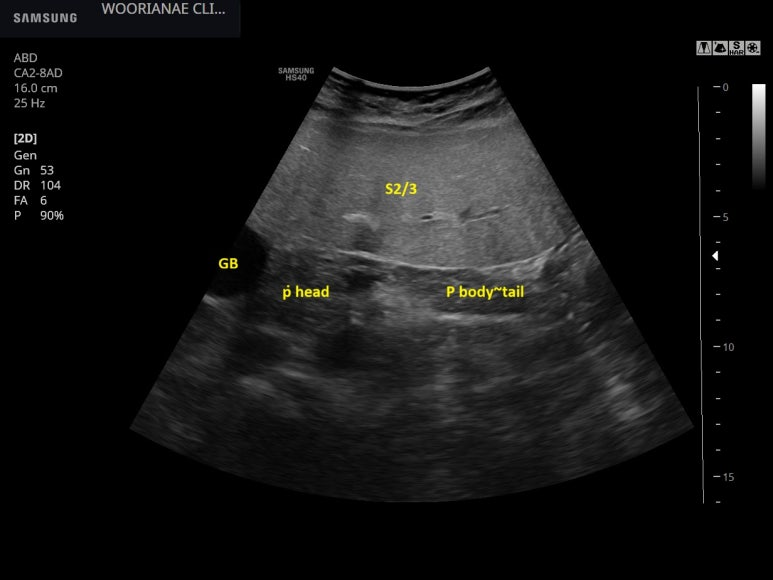

왼쪽간의 관찰시 뚜렷한 간비대가 인지되고 (아래까지 내려온), 내부의 혈관도 상대적으로 직경이 작아 보인다.

담낭에 오니가 있는것 처럼 보였으나 다른 각도에서 확인이 되지 않아 허상으로 판단

간에 의해 밀려서 담낭은 흉곽의 아래에서 관찰할 수 있다. (보통은 갈비뼈 사이에서)

그러나, 작은 모래양 담석들은 움직임을 관찰할수 있다.

알콜 감염에 의한 복수, 담낭오니

쇄골 중앙 너비에서 간의 위아래 길이는 20 cm 에 육박한다.

그리고 우상복부 압통은 담낭이 아니라 전반적인 인간에 해당하는 것을 확인할 수 있었다.

abdominal ultrasound

1. liver parenchyma; moderate to severe FL

hepatomegaly, MCL about 20 cm

liver mass; n-s

2. GB; slugde같이 보이는 것은 artifact? 지속적으로 관찰되지 않음. 프로브로 흔들어 보았을 때 tiny sandy stone들이 떠오르는 것은 관찰됨

프로브로 눌러보았을때 담낭 자체보다는 liver에 대한 전반적 압통임을 확인할수 있음.

3. GB를 다시 관찰함; layer처럼 보이는 소견은 artifact로 보이며, sandy stone이 떠오르는 것을 관찰할수 있음.